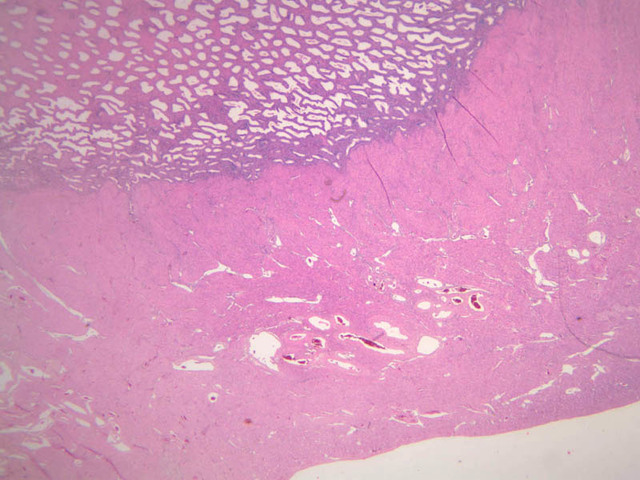

The menstrual phase lasts 1 -5 days, and corresponds to ovarian menstrual phase; i.e., degeneration of corpus luteum with consequent decrease in estrogen and progesterone levels. During this phase the functionalis sloughs off leaving the basalis. Just prior to sloughing, the glands are extremely dilated and tortuous.

This phase occurs during days 7 to 14 and corresponds to the ovarian follicular phase with rising levels of estrogens. The functionalis layer is replaced by growth of the endometrial elements in the basalis. The glands are usually straight tubes extending from the surface. Epithelial cells become taller and accumulate glycogen basal to their nuclei. (slide B-93 [2.5x, 10x, 20x, 40x]; B-97 [2.5x, 10x, 20x, 40x])

This phase occurs on days 15 to 27 and corresponds to the ovarian luteal phase characterized by rising levels of progesterone. The epithelial cells begin to secrete a mucoid fluid rich in nutrients, especially glycogen. The glands become highly coiled and folded and toward the end, very distended. The density of the stroma lessens as it becomes edematous. (slides B-99 [2.5x, 10x, 20x, 40x] [2.5x, 10x, 20x, 40x]; B-100 [1x, 2.5x] [2.5x, 10x, 20x, 40x] [2.5x, 10x, 20x, 40x])